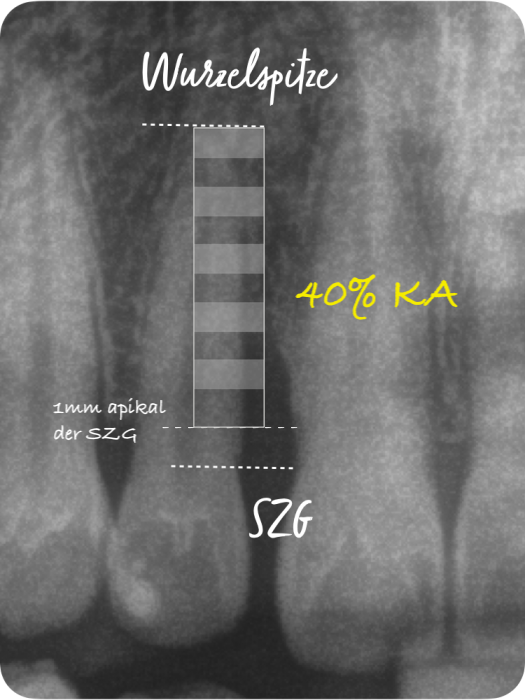

Der Grad enthält Informationen zur Progressionsrate der Erkrankung und dem Vorliegen von patientenspezifischen Risikofaktoren (Nikotinkonsum und Diabetes/HbA1c). Die Progressionsrate kann direkt anhand von Vorbefunden abgeschätzt werden oder indirekt durch den sogenannten Knochenabbauindex (KA %/Alter). Dabei wird der Zahn auf dem Röntgenbild berücksichtigt, der den stärksten marginalen Knochenabbau hat. Das Vorliegen von Risikofaktoren kann zu einem Upgrade führen. Fehlen diese Risikofaktoren, führt das aber nicht zu einem Downgrade.